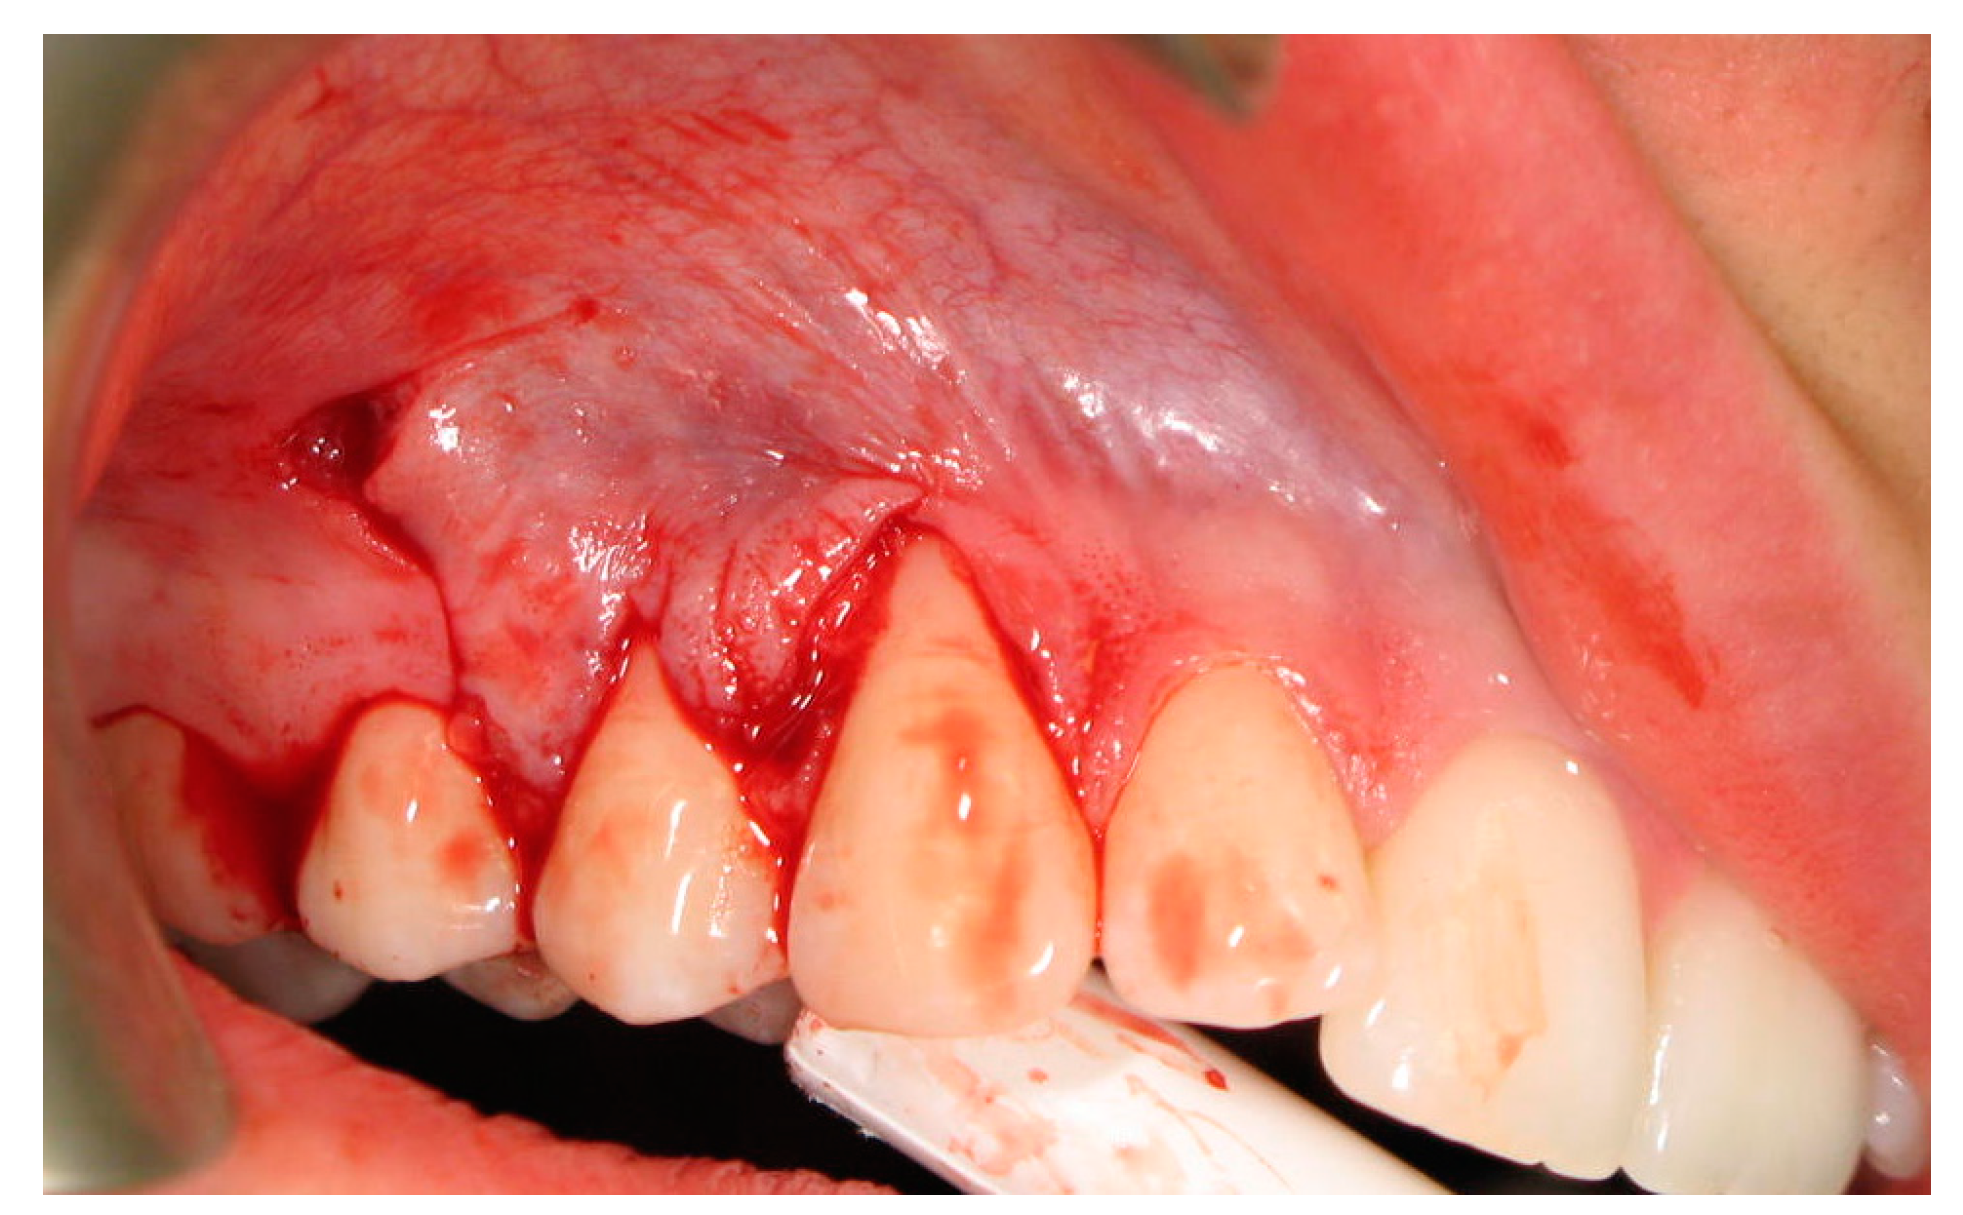

:1. Introduction

2. Materials and Methods

2.3. Surgical Procedures